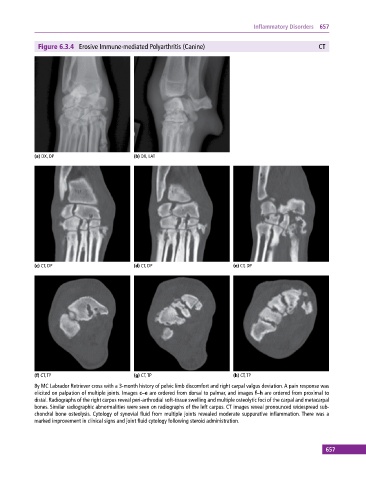

Figure 6.3.4 Erosive Immune‐mediated Polyarthritis (Canine) CT

8y MC Labrador Retriever cross with a 3‐month history of pelvic limb discomfort and right carpal valgus deviation. A pain response was

elicited on palpation of multiple joints. Images c–e are ordered from dorsal to palmar, and images f–h are ordered from proximal to

distal. Radiographs of the right carpus reveal peri‐arthrodial soft‐tissue swelling and multiple osteolytic foci of the carpal and metacarpal

bones. Similar radiographic abnormalities were seen on radiographs of the left carpus. CT images reveal pronounced widespread sub-

chondral bone osteolysis. Cytology of synovial fluid from multiple joints revealed moderate suppurative inflammation. There was a

marked improvement in clinical signs and joint fluid cytology following steroid administration.